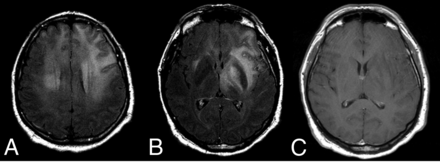

NK/T-cell lymphoma presenting with a lymphomatosis cerebri radiologic pattern (A–C). Patched and diffuse, bilateral and asymmetric, deep and subcortical, hyperintense lesions on FLAIR (A and B) without contrast enhancement (C).